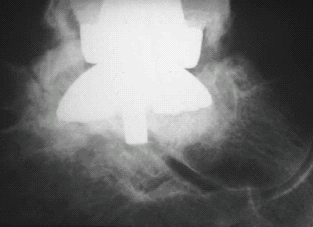

Early total knees were available in only one size. Often the tibial

component was prone to subsidence (Fig. 5A). Today's tibial components are

available in multiple sizes allowing better prosthetic support through the

expansion of support surface area (Fig. 5B).

Fig. 5: A, Subsidence of a single-sized tibial total knee component with

inadequate base plate coverage. B, Newer base plates improve bone coverage

for better support.

Fig. 6: Smaller surface area for support at ankle.

of up to 5.5 times body weight on a much smaller surface area. This greatly

increases the load per unit area (Fig. 6).